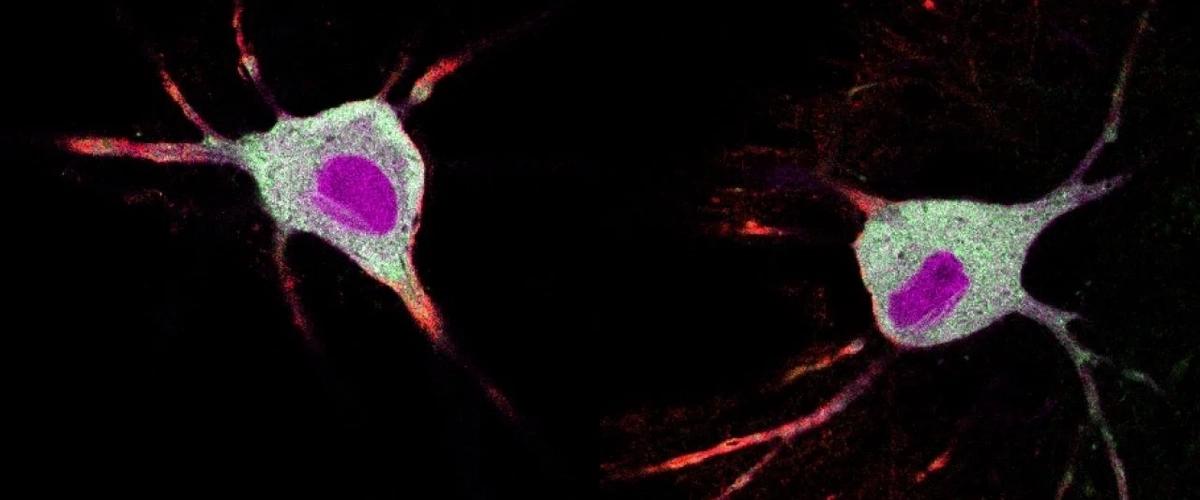

В качестве решения проблемы команда из Калифорнийского университета Дэйвисе разработалаинструмент CaST для отслеживания нейронов и молекул, активируемых в мозге психоделиками. CaST оценивает изменения внутриклеточной концентрации кальция — почти универсального индикатора для оценки активности нейронов.

В первых экспериментах CaST продемонстрировал карты областей префронтальной коры головного мозга мышей, активированных псилоцибином. В дальнейшем ученые намерены изучить по ним активность генов и белков на фоне введения препаратов по сравнению с плацебо. Эти данные помогут проследить пошаговый процесс терапевтического воздействия, чтобы в перспективе получить возможность корректировать лечение для повышения эффективности и снижения рисков побочных эффектов.